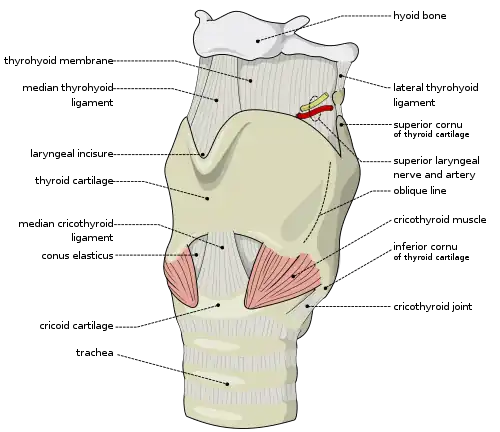

Surgical airways

Surgical methods for airway management rely on making a surgical incision below the glottis in order to achieve direct access to the lower respiratory tract, bypassing the upper respiratory tract. Surgical airway management is performed as a last resort in cases where tracheal intubation has failed, is not feasible, or is contraindicated.[19] Surgical methods for airway management include cricothyrotomy and tracheotomy.[19][20]

Cricothyrotomy

A cricothyrotomy is a procedure during which an incision is made through the cricothyroid membrane, allowing an artificial airway to be placed in the trachea. It is the first-line surgical procedure to access an airway in an emergency because it can be performed more quickly than a tracheotomy and is less likely to cause bleeding and damage to thyroid tissue.[19][20] A cricothyrotomy creates a temporary airway that can be used until a more definitive airway can be secured.[20] A cricothyrotomy is typically performed as an emergency procedure when other airway management attempts have failed and the patient is at risk of asphyxiation. The most common acute complications are bleeding, tracheal cartilage laceration, tracheal perforation, infection, subglottic stenosis, and voice changes. The procedure is frequently performed by an otorhinolaryngologist (an ear, nose, and throat surgeon) if available or an anesthesiologist.[21][22]